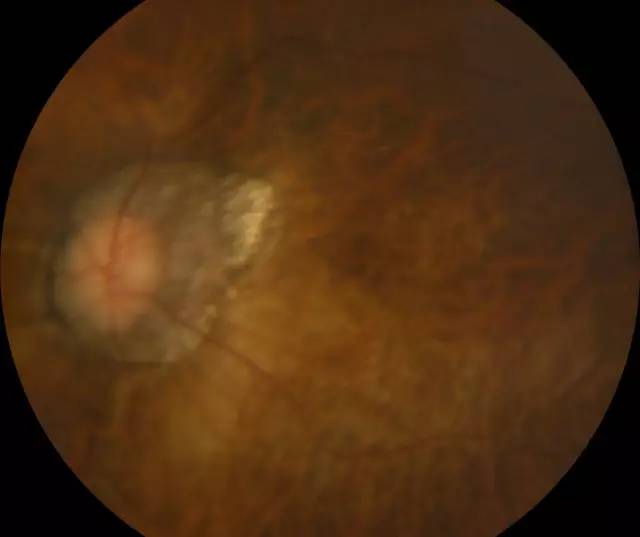

肖先生左眼术前眼底照相图